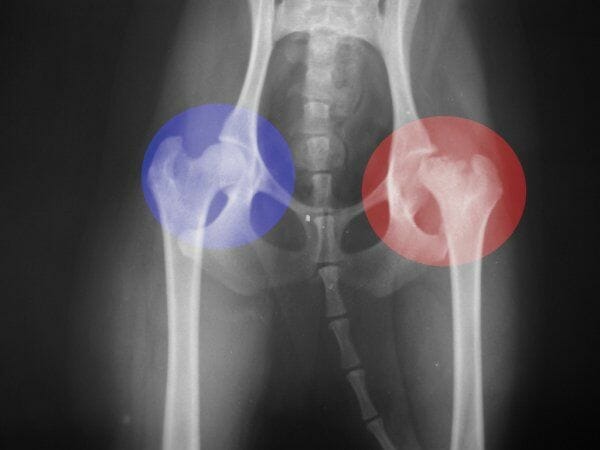

Quiero que veas la siguiente radiografía para que te ubiques:

Si ves, lo que está en el círculo rojo es la cadera y la cabeza del fémur, ve que esa «esfera» no está tan redondeada ni es continua en comparación con la del círculo azul (la parte final superior del fémur, que es como una bola que embona en esa oquedad de la cadera.

Esa “esfera” debe estar perfectamente lubricada (líquido sinovial) y perfectamente fijada (por ligamentos), esto permite el movimiento de las piernas, lo que nos ayuda a caminar, principalmente.